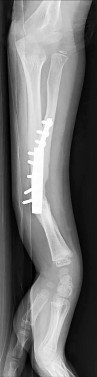

An 8-year-old, 35 kg boy sustains a transverse midshaft fracture of the right femur. He is treated with titanium elastic nails (TENs). What is the most common complication associated with this surgical treatment?